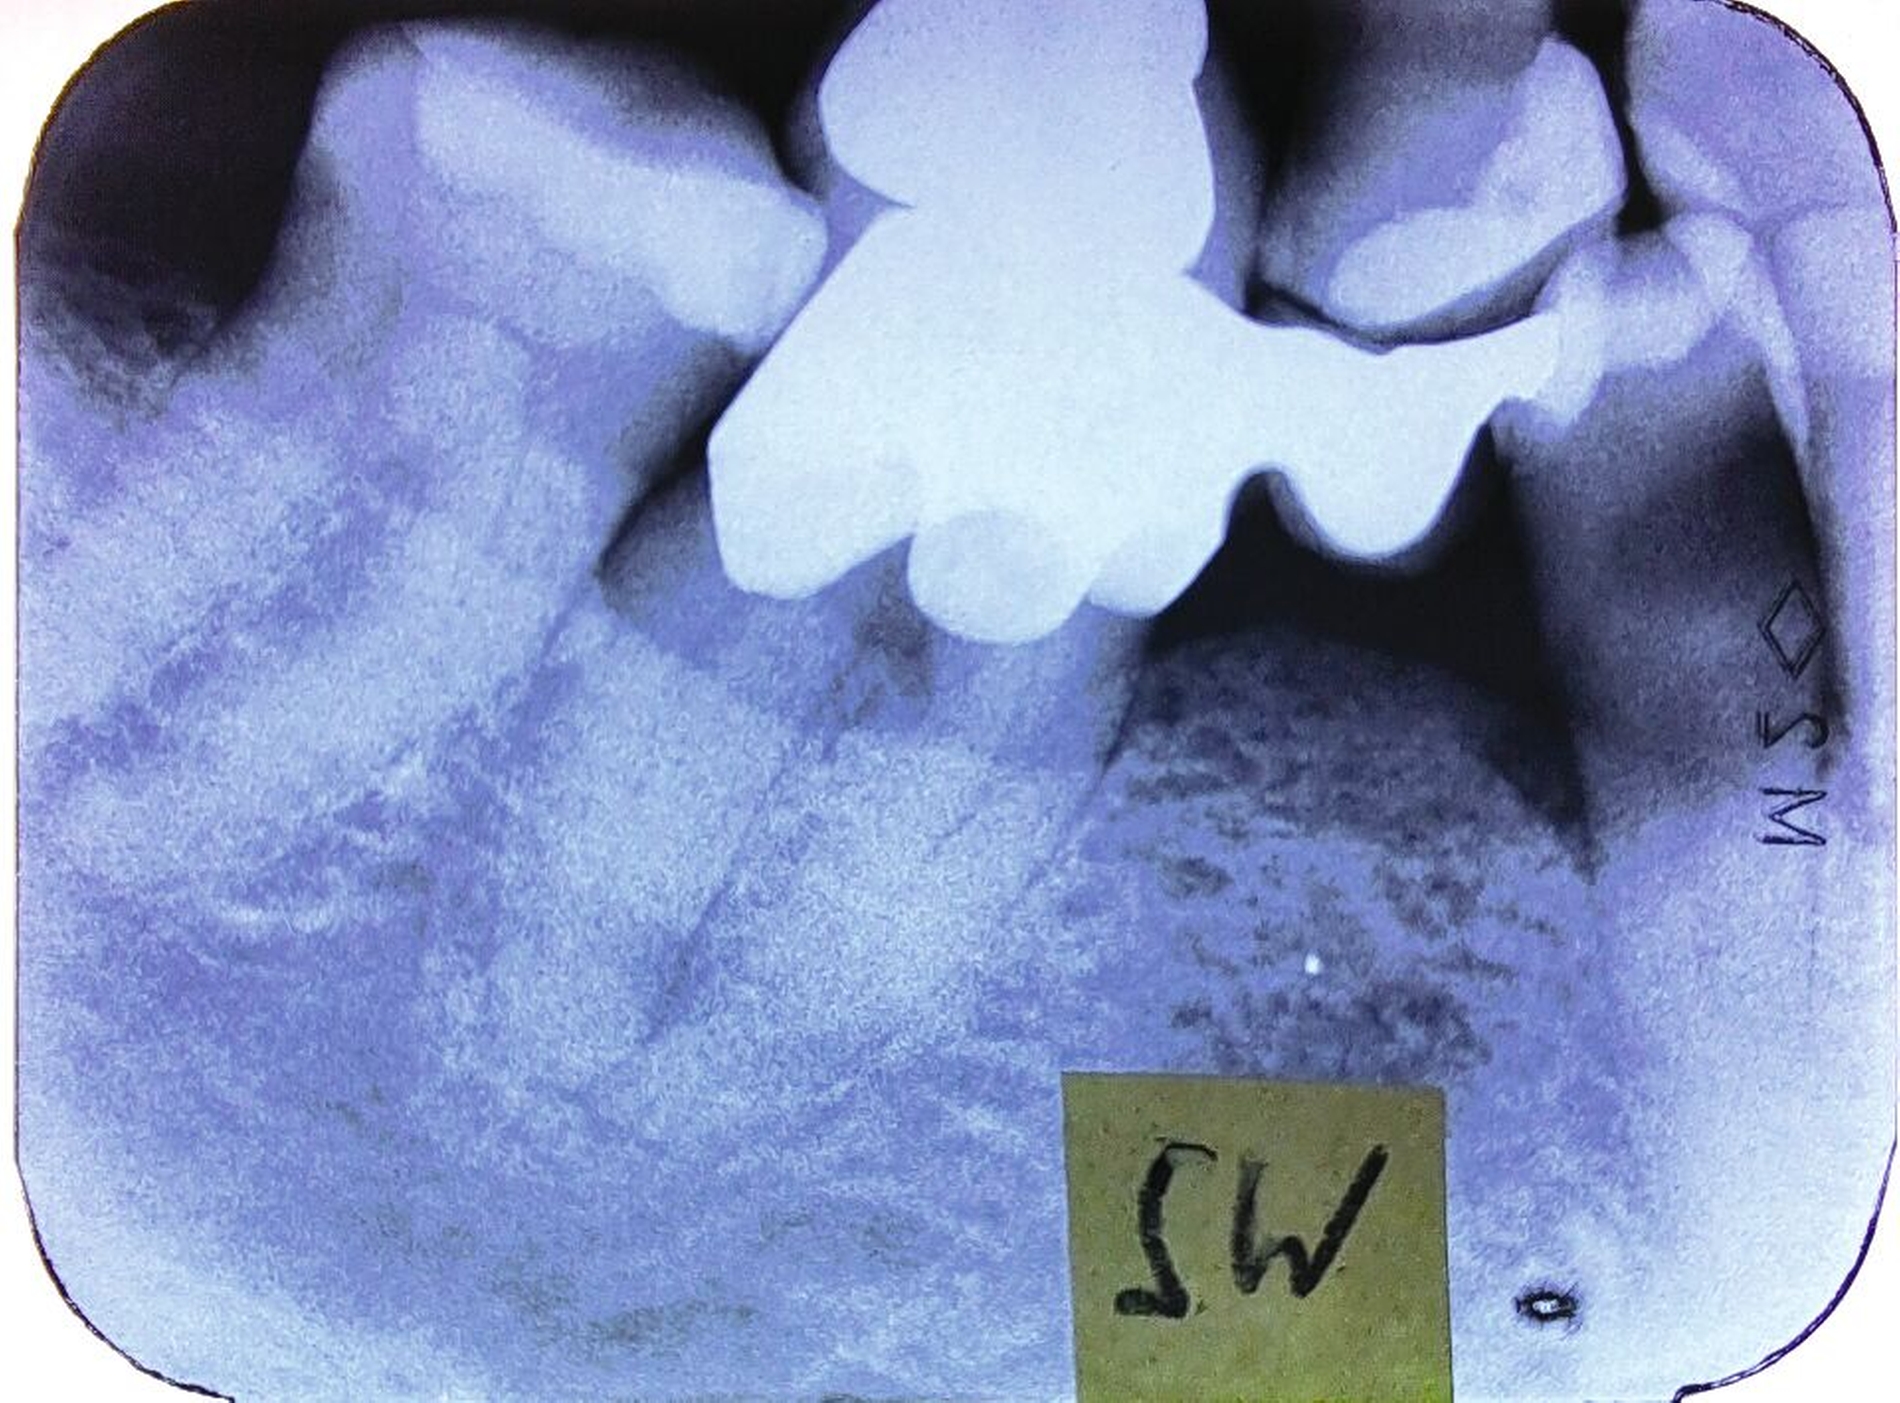

In den Abbildungen werden drei Fallbeispiele vorgestellt, bei denen alle Brücken noch in situ sind: